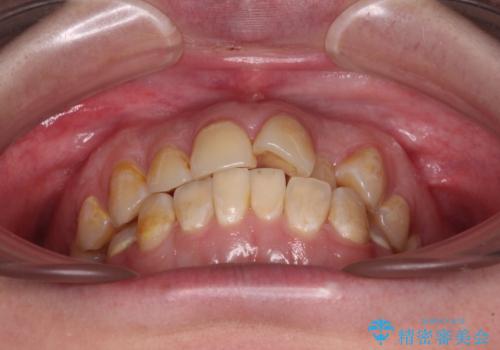

- 前歯のデコボコとクロスバイトが気になり、インビザラインによる矯正治療を希望して来院された患者様です。

上顎側切歯(上の真ん中から2番目の歯)が舌側転位している場合、無理して動かそうとすると歯髄壊死を起こすリスクが高い印象があります。

インビザライン単体でも治療は可能ですが、安全策としてインビザラインで歯列を移動する前に上顎前歯をワイヤー矯正で整え、その後上下歯列をインビザラインにて矯正治療を行うこととしました。

舌側転位している側切歯特有の、切縁の位置が不揃いであったり、根元が内側に引っ込んだ状態であったりという、インビザライン独特の仕上がりになることなく、きれいに整った歯列とすることができました。